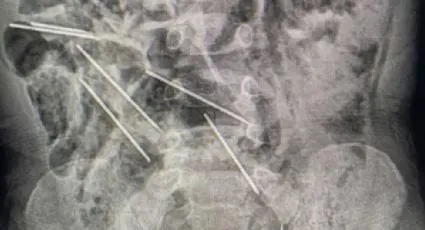

Este sábado en Perú, un nene tuvo que se operado de urgencia por haberse tragado ocho agujas hipodérmicas que se utilizaban para inyectar medicamentos en vacas mientras su madre estaba trabajando en la finca.

Los especialistas de la salud se demoraron dos horas aproximadamente en concluir la compleja intervención para sacar las agujas que se encontraban dispersas en el estómago y el tracto intestinal del nene.